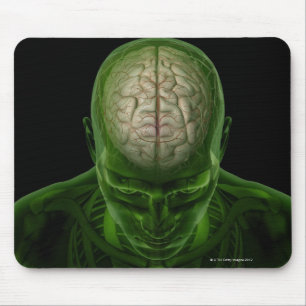

Impressão Em Tela Imagem conceptual do cérebro humano 6

PreçoR$ 589,00